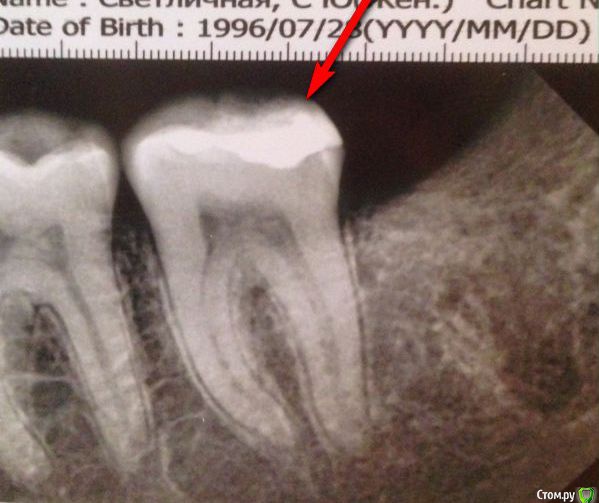

София С Опубликовано 22 ноября, 2017 Поделиться Опубликовано 22 ноября, 2017 Здравствуйте, уважаемые специалисты!После лечения ( уже второй раз ) появилась лёгкая боль при попадании твёрдой частички пищи на задний край пломбы в 37. Зуб лечили 3 месяца назад, боль не увеличивается, но и не исчезает. Четыре месяца назад был удалён 38. Возраст 21 год. Прошу вас посмотреть снимок, и прокомментировать. Ссылка на комментарий

red_butler Опубликовано 22 ноября, 2017 Поделиться Опубликовано 22 ноября, 2017 на снимке все нормально. В идеале замена пломбы на керамическую вкладку Ссылка на комментарий

igorstom Опубликовано 22 ноября, 2017 Поделиться Опубликовано 22 ноября, 2017 Снимок является дополнительным методом диагностики. Остальное нужно увидеть, потрогать, пощупать, постучать, подавить. Только тогда можно будет точно сказать причину Вашего беспокойства. А так причин возникновения боли при накусывании много. По Вашему снимку ничего предосудительного не видно. Разве что большая по площади пломба, с вытекающими последствиями. Да, можно ещё примерно возраст определить. На мой взгляд Вам по снимку примерно около 20-25 лет. Серьёзным видом спорта не увлекаетесь, не курите. Ссылка на комментарий

igorstom Опубликовано 24 ноября, 2017 Поделиться Опубликовано 24 ноября, 2017 Я пойду еще глубже, вам 21 год, по задиаку вы лев, занимаетесь спортом но не профессионально, табаком не увлекались, беспокоит вас зуб нижний с лева для вас, после лечения был дискомфорт, он не проходит, если что-то кусать им , возникает боль. Открою тайну, вам нужно идти к стоматологу. Пломба завышена! Занавес!Ёрничать не нужно. На рентгеновском снимке виден размер пульповой камеры. Просвет в каналах достаточно широкий, даже при наличии обширной пломбы. Что говорит о молодом возрасте и отсутствии нарушений микроциркуляции. Межзубная костная перегородка нормальной высоты. Но Вы астролог, откуда Вам это знать? И да, очень много орфографических ошибок ("Вы" пишется с большой буквы, перед "но" ставится запятая, "с лева" пишется слитно). Занавес! 1 Ссылка на комментарий